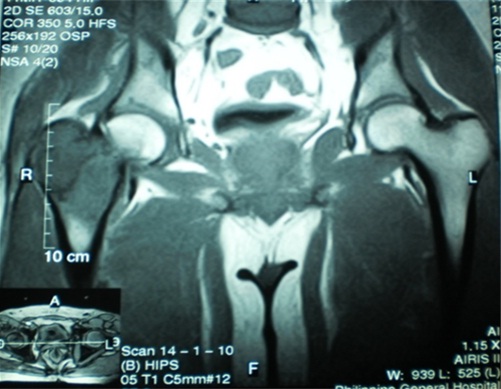

Two weeks prior to surgery, the patient’s pain increased in intensity up to a VAS score of 9/10. He did not recall any incident of fall or trauma. His limp worsened and was unable to put weight on his right lower extremity. He was eventually brought to our institution’s out-patient clinic. After initial assessment from the clinic’s triage, the patient was referred to our institution’s orthopedic and musculoskeletal tumor service. Physical examination done both by the orthopedic-musculoskeletal tumor specialist and orthopedic resident, indicated leg length shortening of 0.5 cm on the right lower extremity, right hip tenderness upon palpation, and a positive heel pound test. No skin lesions, palpable mass, nor lymphadenopathy were noted. The modified Musculoskeletal Tumor Society rating functional (MSTS) score was 4/30. Repeat plain radiographs of the hip revealed a pathologic fracture of the right femoral neck at the area of the lesion (Figure 1). The proximal femoral lesion was characterized as epi-metaphyseal, osteolytic with well demarcated borders, with endosteal expansion, cortical break, and has soft tissue extension anteriorly; but without any matrix. The lesion extended from the femoral neck up to the base of the lesser trochanter. The patient was admitted for further work-up and his right lower extremity was placed in skin traction. Magnetic resonance imaging of the hip confirmed a well delineated homogenous 8x7 cm lesion from the greater trochanter up to the level of the base of the lesser trochanter (Figure 2). A pre-operative tru-cut biopsy was done in the ward to exclude other differential diagnosis such as aneurysmal bone cyst and other primary bone tumor. The results confirmed giant cell tumor of the bone. The radiologic grade of the tumor was a Campanacci III due to the anterior cortical break and soft tissue extension, while the clinical and histologic grade was an Enneking 3 (for benign lesions). A pre-operative chest X-ray was done to rule out pulmonary metastasis, and showed negative results. The authors decided to pursue wide excision and perform total hip replacement due to the patient’s age and function, high recurrence for GTCb, along with the extensiveness of the lesion and the cortical break. Prosthesis specifications that were considered included a custom-made proximal femur endoprosthesis or a proximal femoral allograft composite. However, due to financial constraints and unavailability of a proximal femur allograft, a calcar-replacing femoral stem was selected due to the involvement and possible excision of the calcar femorale and lesser trochanter.

Figure 2: Magnetic resonance imaging coronal T1 image demonstrates a well delineated homogenous 8x7 cm lesion from the greater trochanter up to the level of the base of the lesser trochanter.